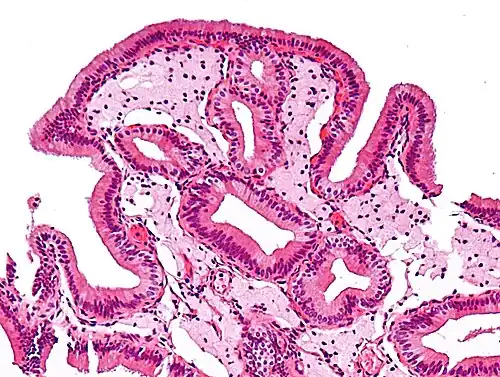

-

Micrograph of cholesterolosis of the gallbladder